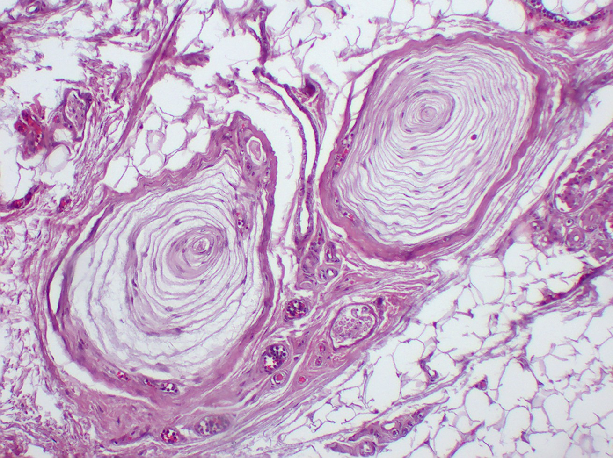

图7 环层小体光镜图 (HE染色)